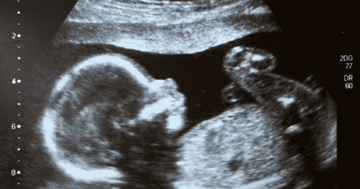

In ideal circumstances, if you find out that you're pregnant, the next thing to do is schedule your first ultrasound appointment.

During an ultrasound, doctors check to see if the baby is alive, developing properly for gestational age, and is present. It also detects any developmental issues affecting you or your baby.

That is, if the foetus is placed within the womb and not the fallopian tubes. This is usually called a dating scan. The earlier you have this scan the more accurate it is for determining your due date. It is usually performed at 6 to 8 weeks of pregnancy after a positive pregnancy test.

When the little one shows a heartbeat, it confirms that it is a viable pregnancy. It is after 22 to 25 days of gestation that the foetal heart beats for the first time.